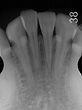

初期段階では、炎症が歯肉に限局しておこっているため、歯肉炎と呼ばれますが、やがて炎症が歯の周りの組織に広がると、歯周炎へと進行していきます。歯周炎になると、歯を支えている骨(歯槽骨)が溶けていきます。これを放置していると、歯肉から膿(うみ)が出てきたり、歯がグラグラしてきたりして、やがて歯が抜け落ちます。歯肉炎では、歯肉は炎症のため赤く腫れていますが、歯槽骨の吸収はありません。一方、歯周炎では、炎症が歯周組織に広がるため、歯槽骨の吸収や歯肉の退縮が見られます。